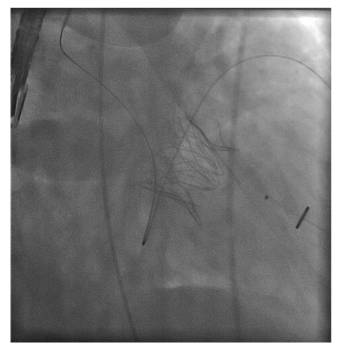

Repair Device

Repair the Chorda –Neo/Chord

Trans-catheter Mitral valve repair - Annuloplasty